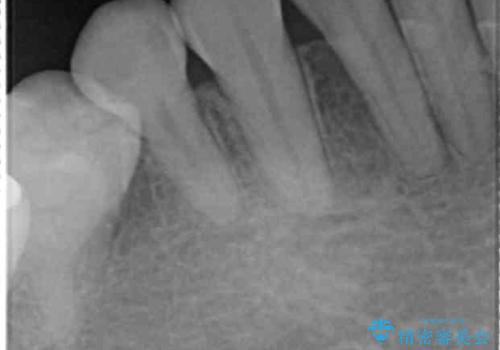

- 子供のころに4本抜歯してワイヤー矯正をしたとのことでした。

最近右下の犬歯の根の先付近の歯茎に何かできており、違和感があるとのでした。

CTでみたところ、下の犬歯が内側に倒れこんでおり、根の先が顎の骨から出かかっている状態でした。おそらくその影響で犬歯の神経が失活してしまったのであろうと思われます。(フェネストレーションといいます)

検査した結果下の両側の犬歯の神経が失活しており、根の治療が必要な状態でした。